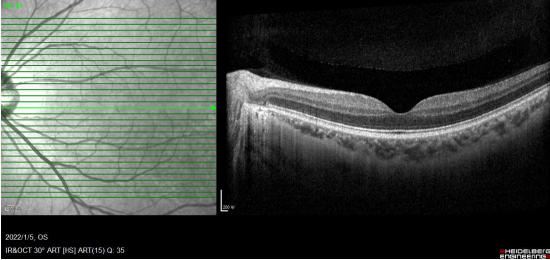

术后一周,老杜复查结果显示,恢复良好。“视物变形改善,黄斑水肿需要3-6个月的时间恢复和观察,好的话视力会提高,否则只能维持现在的视力。”郑宏华博士进一步解释,老杜黄斑前膜到达晚期,黄斑水肿已经产生结构性损伤,尽管手术膜剥了,但如果视网膜形态结构回不去,视力恢复程度就十分有限。幸运的是老杜还是及时止损,下决心手术了,现在视力由术前的0.2,提高到了0.5,黄斑水肿在缓慢消退,神经细胞在缓慢恢复中。

手术后OCT检查,黄斑前膜剥除,黄斑形态缓慢恢复↑

正常的黄斑结构↑